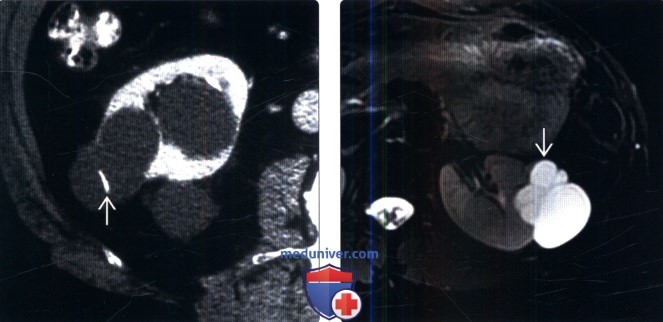

2. История болезни

44-летняя женщина поступила в наше хирургическое отделение с жалобами на наличие хронических болей в эпигастрии и умеренной лихорадки. Для этих симптомов была проведена рентгенологическая визуализация через УЗИ верхних отделов брюшной полости, которая продемонстрировала мультикистозное поражение левой почки. При этом анамнезе при поступлении при системном клиническом обследовании выявлено гладкое, безболезненное образование в левой подчревной области.Клиническое обследование, касающееся всех других систем, показало нормальные результаты. Поэтому была проведена компьютерная томография (КТ) верхних отделов живота с контрастированием, которая подтвердила данные УЗИ (рис. 1) и показала гиподенсивное мультикистозное образование с кальцифицированными толстыми стенками, характерное для эхинококкового заболевания.

Эхография правой почки показала нормальный размер 121 мм и толщину паренхимы 23 мм, без камней и обструкции, но в левой почке размером 165 мм и толщиной паренхимы 18 мм одна типичная киста размером 120×93 мм было замечено. Компьютерная томография детально проиллюстрировала кисту (рис.1). Результат УЗИ и КТ показал простую кисту при Р/О раке и без четкого диагноза, пациенту была назначена цистэктомия, и образец был отправлен в отделение патологии. Результаты показали окончательный диагноз эхинококковой кисты, и в срезе ткани были видны протосколексы (рис. 2). После операции пациентка выписана из стационара без каких-либо симптомов. После диагностики патологоанатома больной получал альбендазол 10 мг/кг ежедневно в течение 12 недель. Пациент наблюдался в течение 3 месяцев, каждые 2 недели проводилось УЗИ, анализ печени, анализ мочи, общий анализ крови и тест на количество тромбоцитов для поиска кист.В последующем пациент наблюдался ежемесячно в течение 1 года, рецидивов не наблюдалось.

КТ почек.

Правая почка нормальных размеров 23×121 мм, без камней и обструкции. Левая почка размером 18×165 мм и наличием типичной кисты размером 93×120 мм.